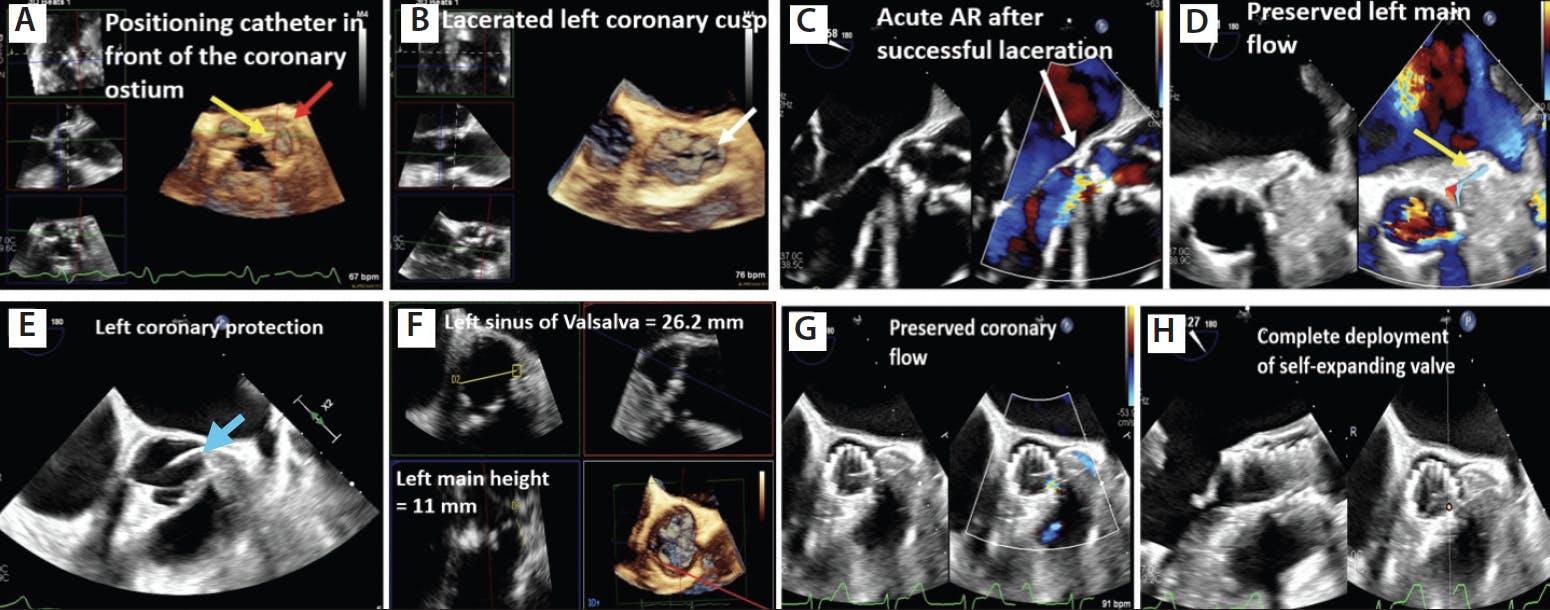

With the help of multiplanar imaging and three-dimensional (3D) imaging at the time of TAVR, TEE helps identify the left main occlusion at the time of balloon inflation for borderline cases, guide snorkel procedures, and identify the laceration point in front of the coronary ostium to guide optimal laceration of the leaflet, as well as aid use of newer investigational devices such as ShortCut (Pi-Cardia), a dedicated leaflet splitting device.18 Additionally, TEE also helps confirm the measurements obtained from CT prior to commencement of the procedure. Figure 3 shows examples of the use of TEE in coronary protection.

Figure 3. Three-dimensional multiplanar imaging showing position of the BASILICA catheter (yellow arrow) in front of the left main coronary artery (red arrow) (A). Laceration of the left coronary cusp during BASILICA procedure (white arrow) (B). Color-compare imaging of the aortic valve showing acute AR following leaflet laceration (white arrow) (C). Preserved coronary blood flow noted in the left coronary system following valve implantation (D). Example of coronary protection with prewiring of the coronary artery (blue arrow) (E). Measurement of the sinus dimensions using multiplanar reconstruction (MPR) imaging in a case with borderline sinus measurement (F). TEE short-axis image demonstrating preserved space in the sinus and flow into the left coronary (G). The self-expanding valve was completely deployed under constant visualization (H).